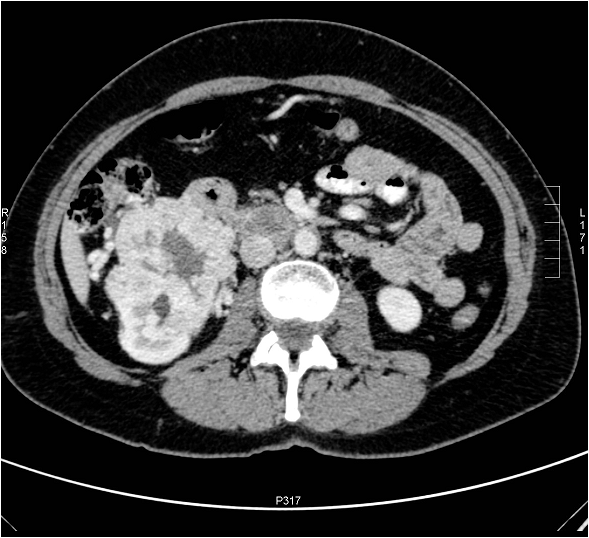

16.2.4. Tumors of extra-renal origin

Non-renal tumors of the kidney include: lymphoma, leukemia, myeloma and metastases.

The kidney does not contain lymphoid tissue. Nevertheless, it can be infiltrated by lymphomas. Non-Hodgkin lymphomas more frequently involve the kidneys than Hodgkin disease.

On US examination a solitary, hypoechoic, homogenous mass is generally detected however; multiplex lesions can be also frequently seen. The secondary lesion on the CT scan usually appears as a hypodense, slightly contrast enhancing mass. MRI can verify the provisional diagnosis of myeloma if the lesion shows intermediate signal on T1 and high signal on T2 weighted sequences.

Invasion of the leukemia cells involves both kidneys thus, the renal parenchyma shows diffuse symmetrical thickening on both sides.

Myelomas can also present with bilateral kidney masses. In addition to the characteristic nephrocalcinosis moderate volume expansion may also be detected. Importantly, contrast administration should be avoided in myeloma patients because the risk of contrast medium induced nephropathy (CIN) is high.

According to autopsy series metastases frequently (20%) involve the kidneys. Their ratio to primary renal tumors is 4:1. However, the clinical picture is usually dominated by the primary tumor. Meanwhile, renal metastases result in occasional hematuria and peri-renal bleeding. Melanomas, colon, breast, and lung carcinomas are the most frequent to metastasize to the kidneys. Metastatic spread often leads to multiplex lesions.

On CT metastases are characteristically seen as small hypodense lesions. These usually show delayed contrast enhancement compared to primary neoplasms. On US solid, hypoechoic lesions can be detected. With MRI metastases show high signal intensity on T2 weighted sequences.